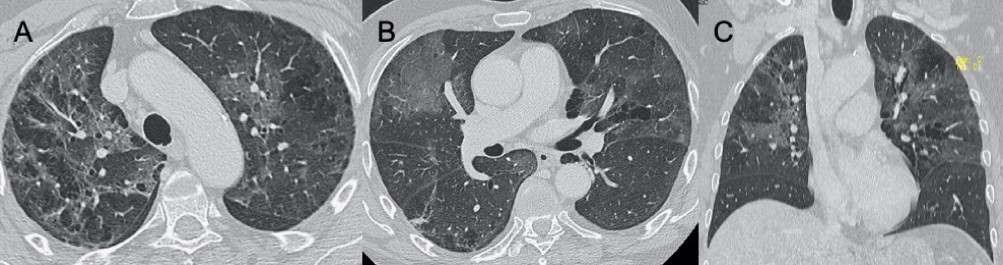

● CXR:單側/雙側GGO,伴或不伴實變區域,主要分布于支氣管血管周圍和胸膜下。

● CT:單側/雙側GGO,伴或不伴實變區域,主要分布于支氣管血管周圍和胸膜下。

圖4 圖(A-D)為一例H1N1相關肺炎并發急性呼吸窘迫綜合征(respiratory distress syndrome,ARDS)的影像,可見彌漫性和雙側GGO以及牽引性支氣管擴張。